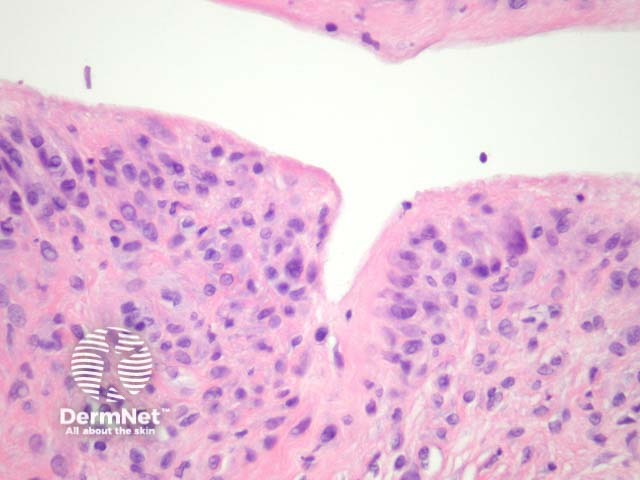

Sections show a irregularly shaped cystic space without an epithelial lining (ie a pseudocyst) surrounded by a dense fibrosis (figure 1). The pseudocyst is lined by a characteristic membrane similar to hyperplastic synovium: the cells of the membrane showed an eosinophilic spindle shaped cytoplasm with processes towards the lumen, which is identical to synovium (figure 2, right hand side; figure 3). It is not uncommon to find foreign material (figure 2, left hand side; figure 4) surrounded by a foreign body reaction and/or synovial metaplasia.

Figure 3